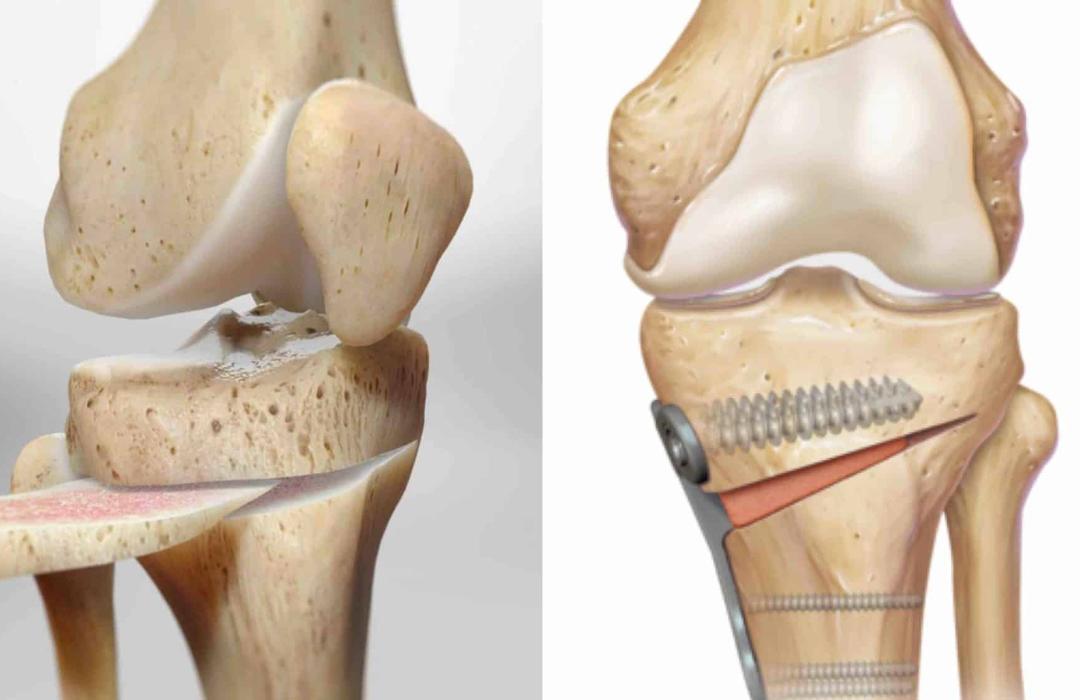

A osteotomia ao redor do joelho é um procedimento cirúrgico que realinha os ossos da perna para redistribuir o peso corporal sobre áreas menos desgastadas da articulação.

É um procedimento em que o osso é cuidadosamente cortado e realinhado para corrigir desalinhamentos que sobrecarregam uma parte do joelho. Depois, ele é fixado com placas e parafusos até cicatrizar na nova posição.